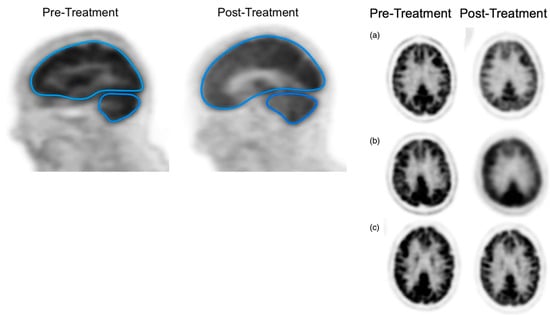

In a recent study, the aim was to compare the effects of treatment—specifically, conventional standard-dose chemotherapy (CDC) versus HDC followed by autologous stem cell transplantation (HDC/ASCT)—on the overall brain glucose metabolism of MM patients [46]. The researchers employed a comprehensive brain [18F]FDG PET measurement approach for this purpose, providing an evaluation of changes in 18FDG metabolism throughout the whole brain (Figure 9) [46]. After treatment, a notable reduction in the GSUVmean (global standardized uptake value mean) was observed in the supratentorial brain and cerebellum of patients who underwent HDC/ASCT (p-values < 0.05) (Figure 9) [46]. Conversely, there were no statistically significant GSUVmean changes after treatment in patients who received CDC (Figure 9). The scientists concluded that a significant decrease in [18F]FDG uptake in the brain after treatment was only observed in patients who received HDC/ASCT [46]. This observation might suggest a tendency for chemo brain to be more prevalent in cases involving HDT [46].

Figure 9.

The left figures depict the use of designated regions of interest (ROIs) for the supratentorial and cerebellum areas within the brain of a multiple myeloma patient. The separation of the supratentorial region from the cerebellum was achieved using the tentorium cerebelli as a reference point. Patients (a,b) received high-dose therapy, whereas patient (c) received conventional chemotherapy, resulting in fewer changes in brain [18F]FDG uptake compared to patients (a,b).